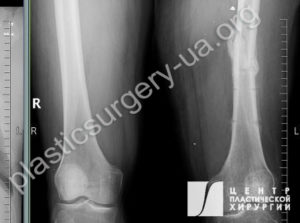

Рис. 31. Фото минно-осколочного ранения голени справа. При поступлении в клинику определяется обширный раневой дефект и огнестрельный перелом большеберцовой кости, с дефектом кости до 4 см. Отломки кости стабилизированы в аппарате внеочагового остеосинтеза. Рис. 32. Рентгенограмма при поступлении в клинику, огнестрельный оскольчатый перелом большеберцовой кости с объемным дефектом до 4 см.

При поступлении в клинику определяется обширный раневой дефект и перелом костей голени В3 с дефектом большеберцовой кости до 11 см. Отломки кости стабилизированы в аппарате внеочагового остеосинтеза. Рис. 38. Результат реконструкции через 4 месяца; рана голени закрыта свободным антеролатеральным перфорантным лоскутом (ALT), размерами 21х10 см, гранулирующая рана стопы закрыта пересадкой кожного расщепленного трансплантата.

Рис. 39. Рентгенограмма левой голени после закрытия дефекта лоскутом. На рентгенограмме определяется открытый оскольчатый перелом 3В ст. костей левой голени, тень избыточных мягких тканей лоскута в нижней 13 голени. Рис. 40. Рентгенограмма левой голени через 24 месяца после травмы. После билокального ЧКДО определяется восстановленный методом дистракционного остеогенеза дефект большеберцовой кости; формирующийся костный анкилоз голеностопного сустава; сросшиеся переломы дистальной 1/3 диафизов обеих костей голени; в дистальном отделе синостоз костей голени. Лодыжки отсутствуют и своими дистальными концами образуют ложные суставы с таранной костью; остеопороз. Опорная функция нижней конечности восстановлена, пациент самостоятельно ходит без дополнительной опоры.